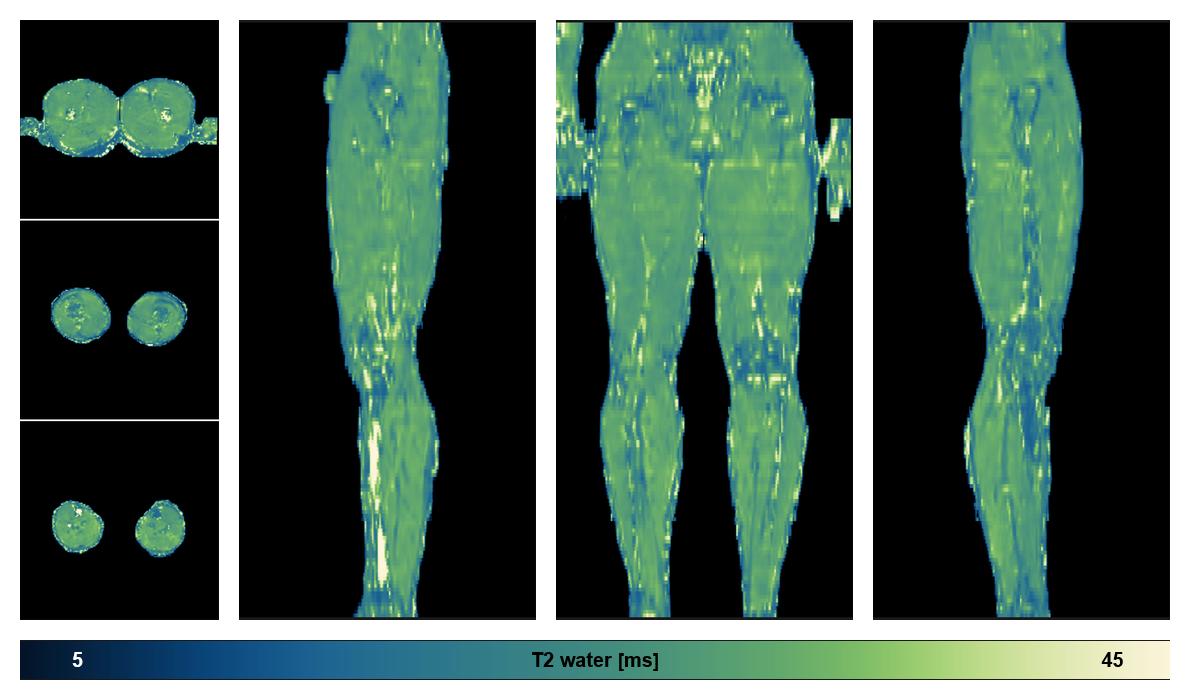

Water only T2 mapping

Multi echo spin echo T2 relaxation time mapping with EPG reconstruction, for information look here».

• Water only signal

The water part of the acquired multi-echo spin echo data.

• Water only T2 relaxation time

The water only T2 relaxation time of the lower extremity obtained from multi echo spin echo t2 mapping with EPG based reconstruction.